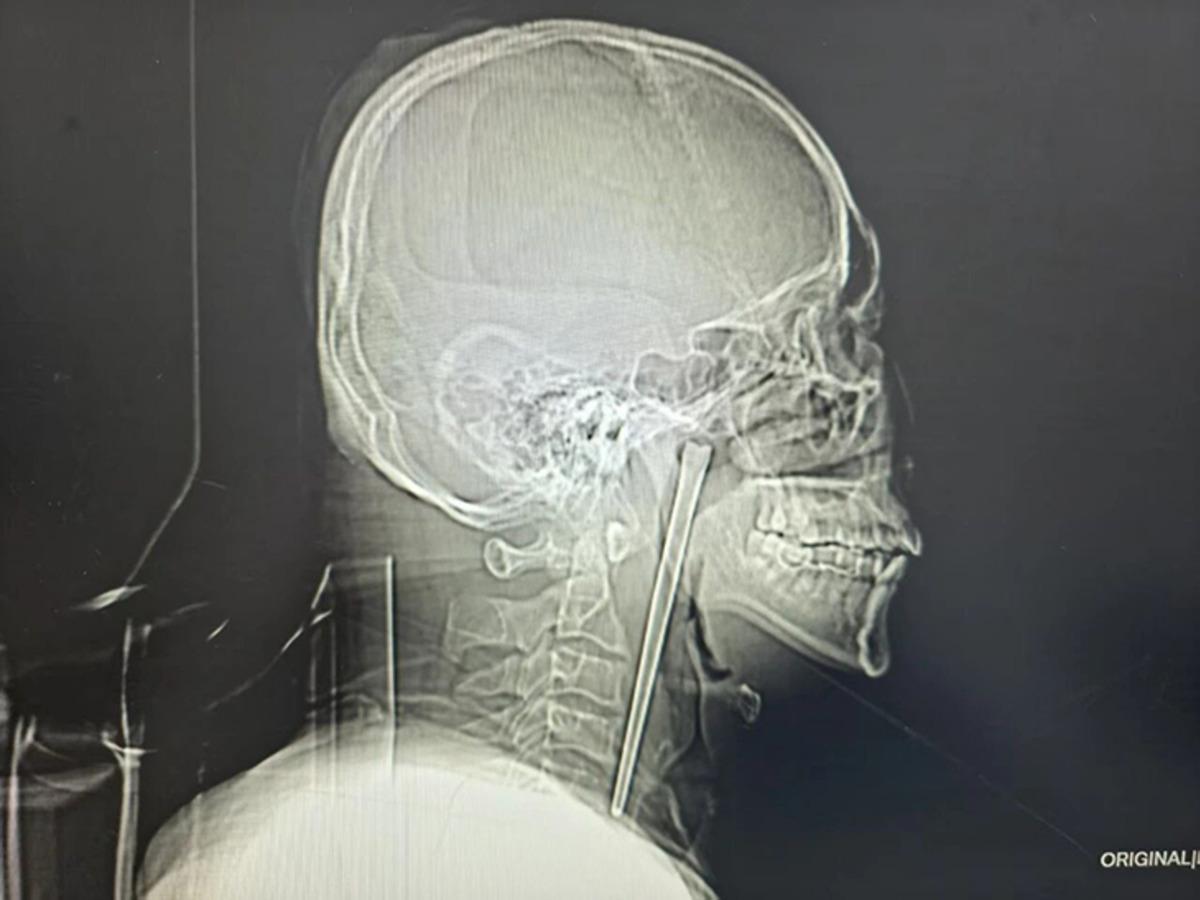

Doktorlar, Wang'ın boğazını incelediklerinde dokularda herhangi bir kanama veya iltihaplanma görmediler. Ancak çekilen röntgen filmi gerçeği tüm çıplaklığıyla ortaya koydu: Boğazın iç kısımlarına yerleşmiş, 12 santimetre uzunluğunda, metal bir şaft duruyordu. Çubuk, her an hayati damarlara zarar verebilecek veya doku hasarına yol açabilecek bir saatli bomba gibiydi.

Dr. Huang Weipeng liderliğindeki sağlık ekibi, hastanın ameliyat korkusunu yenmek için titiz bir plan hazırladı. Boyun bölgesinde kalıcı bir hasar bırakmamak adına minimal invaziv (kapalı cerrahi) yöntem tercih edildi. Ağız içinden yapılan hassas bir müdahaleyle, 12 santimetrelik paslanmaz çelik çubuk, çevre dokulara zarar verilmeden tek parça halinde çıkarıldı.